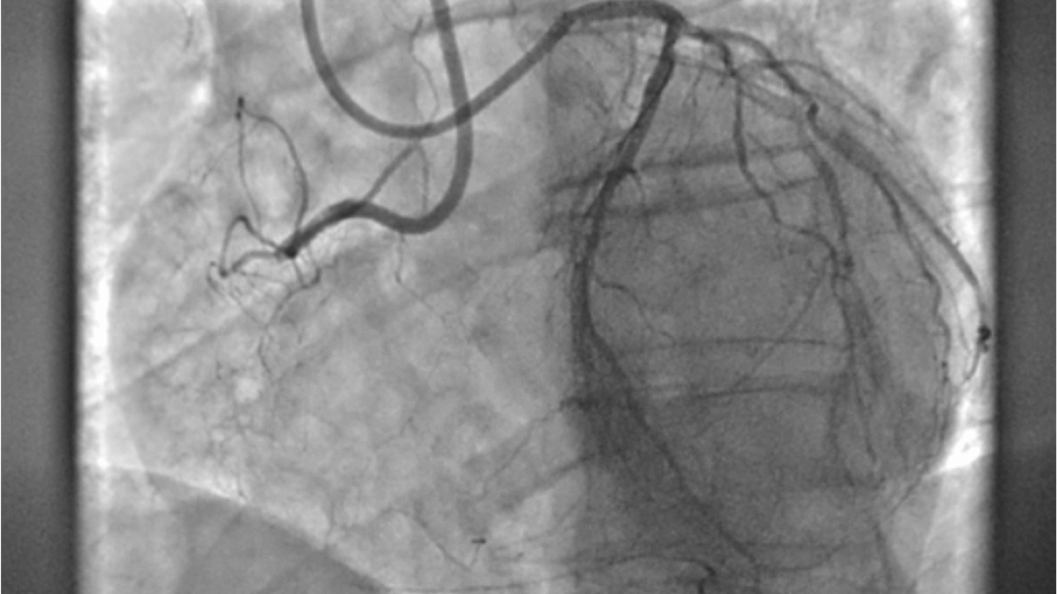

Helps you to assess vascular diseases, from cardiovascular conditions and peripheral vascular disease to pulmonary vascular disease.